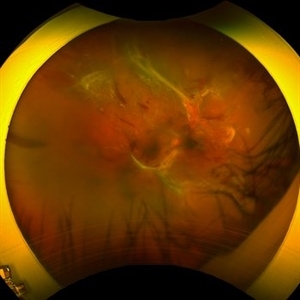

Severe Proliferative Diabetic Retinopathy

Jan 10 2024 by Ahmad B. Tarabishy, MD

33 year old female with 1 month history of vision loss right eye. Severe PDR was noted with VH and a TRD with severe FVP present OD.

Photographer: Sharon Story, Lakeland Eye Clinic

Imaging device: Optos

Condition/keywords: diabetic blindness, fibrovascular proliferation, nonperfusion diabetic retinopathy, peripheral retinal nonperfusion, proliferative diabetic retinopathy (PDR), tractional retinal detachment